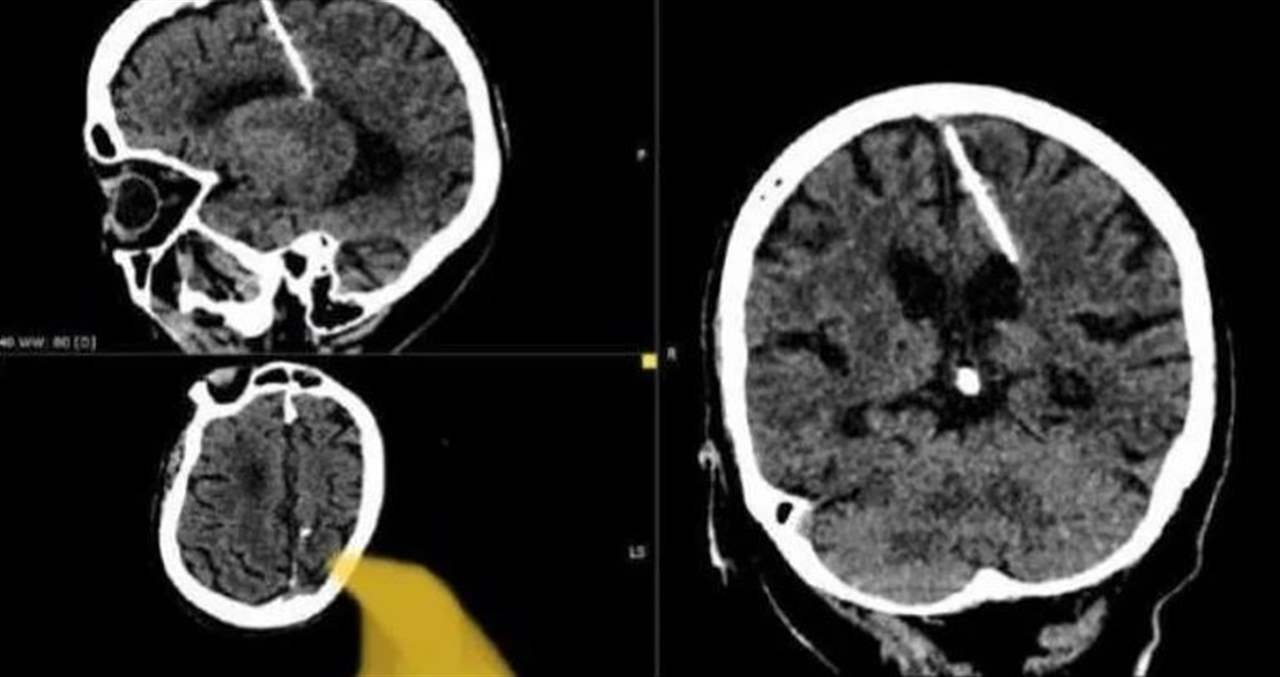

عثر أطباء روس خلال فحص بالتصوير المقطعي على إبرة بطول ثلاثة سنتيمترات موجودة منذ ثمانين عاماً داخل دماغ امرأة مسنّة في أقصى الشرق الروسي.

وقالت إدارة الصحة المحلية "لقد اخترقت الإبرة الفص الجداري الأيسر، لكن لم يكن لها التأثير المقصود، إذ نجت الفتاة".